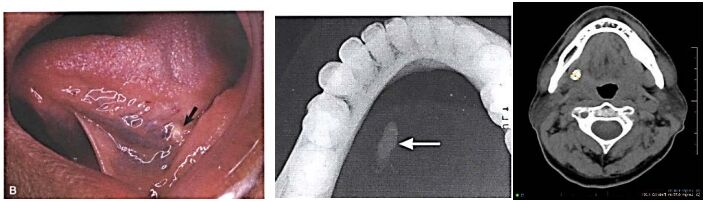

31. 下列是 56 歲男性口腔檢查結果,請問此病灶為何(A) salivary duct stones(B) salivary duct fibrosis(C) salivary duct infection(D) salivary duct necrosis